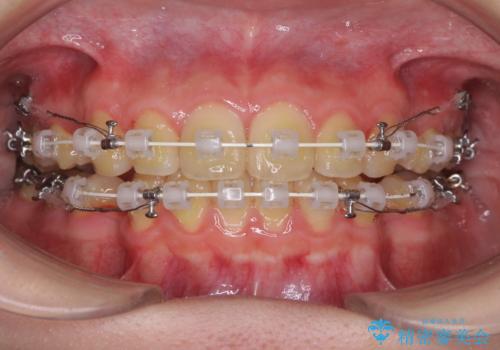

- 審美装置

- 2年3ヶ月

- 10-30回

- 口元が出てるのが気になるとのことで来院されました。

歯のがたつきはあまりなかったのですが、口唇が閉じずらく、口元の突出感が確認できました。

上下左右の歯を1本ずつ抜歯して、そのスペースを利用して口元を引っ込める計画としました。